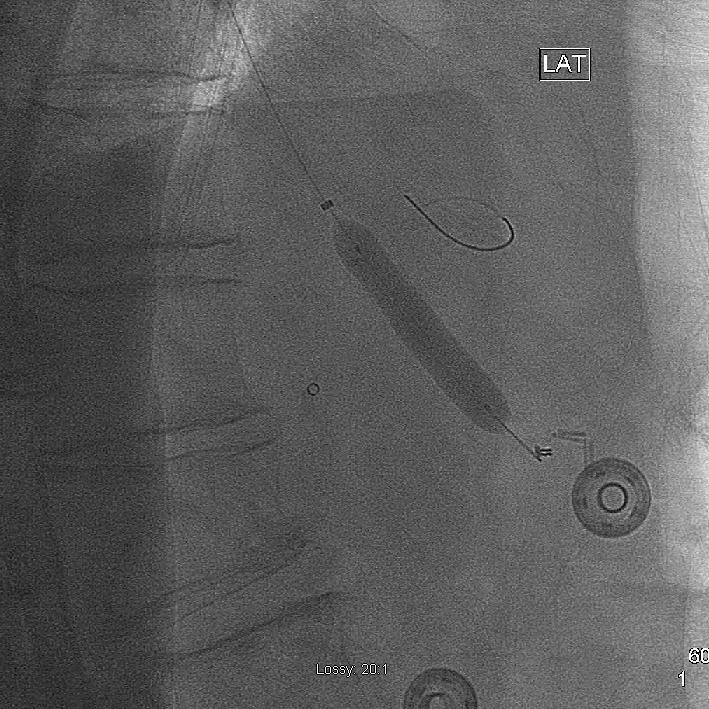

Despite attempts with multiple balloons of varying model and size, we were unable to get across the area of restenosis. The guide catheter was replaced with a Simmons-1 and the lesion re-crossed with a wire, but further efforts to advance a balloon proved futile. At this point, it was decided to switch to a transradial approach, as this would likely provide better guide catheter support. A 5F Multipurpose guide catheter proved a stable platform for subsequent angioplasty (Fig 2).

Mesenteric artery intervention

Angioplasty of the celiac artery with a 7 mm diameter balloon. Note that, when coming from above, the guide catheter is coaxial with the target vessel.